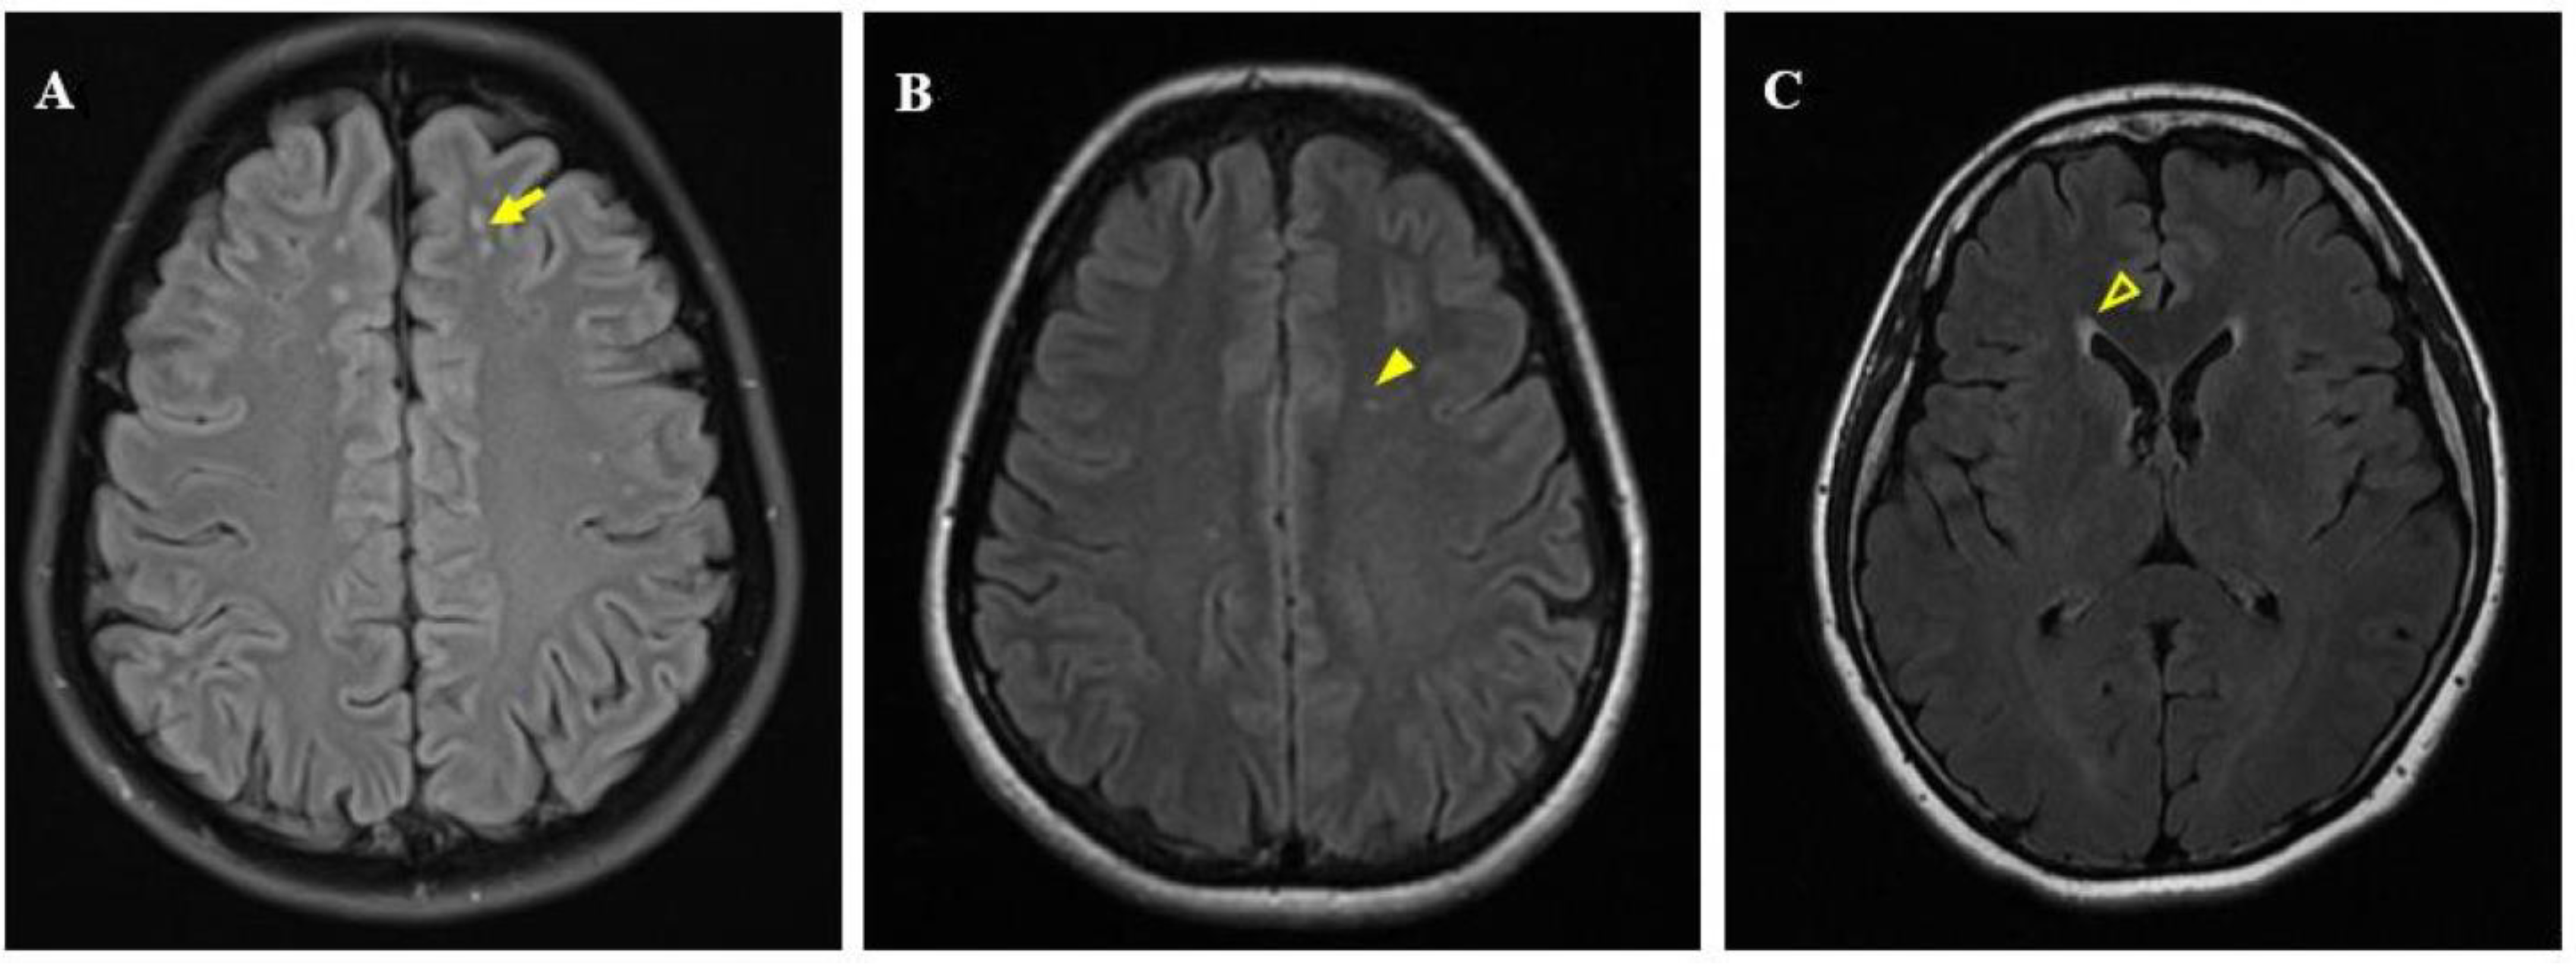

2.5. Image Post-Processing Analysis and WML Evaluation